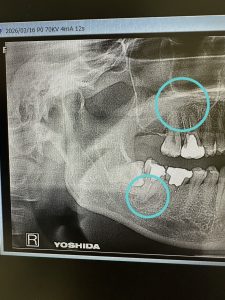

➁

13年振りの来院、力による骨破壊、コンプレッション

syndこれは抜歯しかない

私がやれば、ば良くなります!

インプラントやるかは不明だが、提案、自己投資次第

健康寿命からの逆算